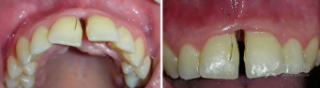

烧伤整形邹普功烧伤科医师

活动背景和目的:我从去年九月份陆续在丁香园写了几十帖有关腋臭微创手术的帖子,受到很多同行老师的关注及跟帖,其中有很多同行老师也在尝试用我的这种方法治疗狐臭,并且收到很好的效果。随着站内外科同行对狐臭微创手术的关注度日渐增高,近期受丁香园邀请,特举办一次关于狐臭微创手术的跟学练活动。这也是本人根据临床工作中的一些手术案例总结的经验,分享给大家一起交流学习。让我们一起做好除臭这件事!各位站友可点击下面狐臭专场链接交流学习(包含本人视频操作教学详解、常见问题讨论和各位站友同行的手术佳作):https://3g.dxy.cn/newh5/view/nodeActivityTopic/270第一期我给大